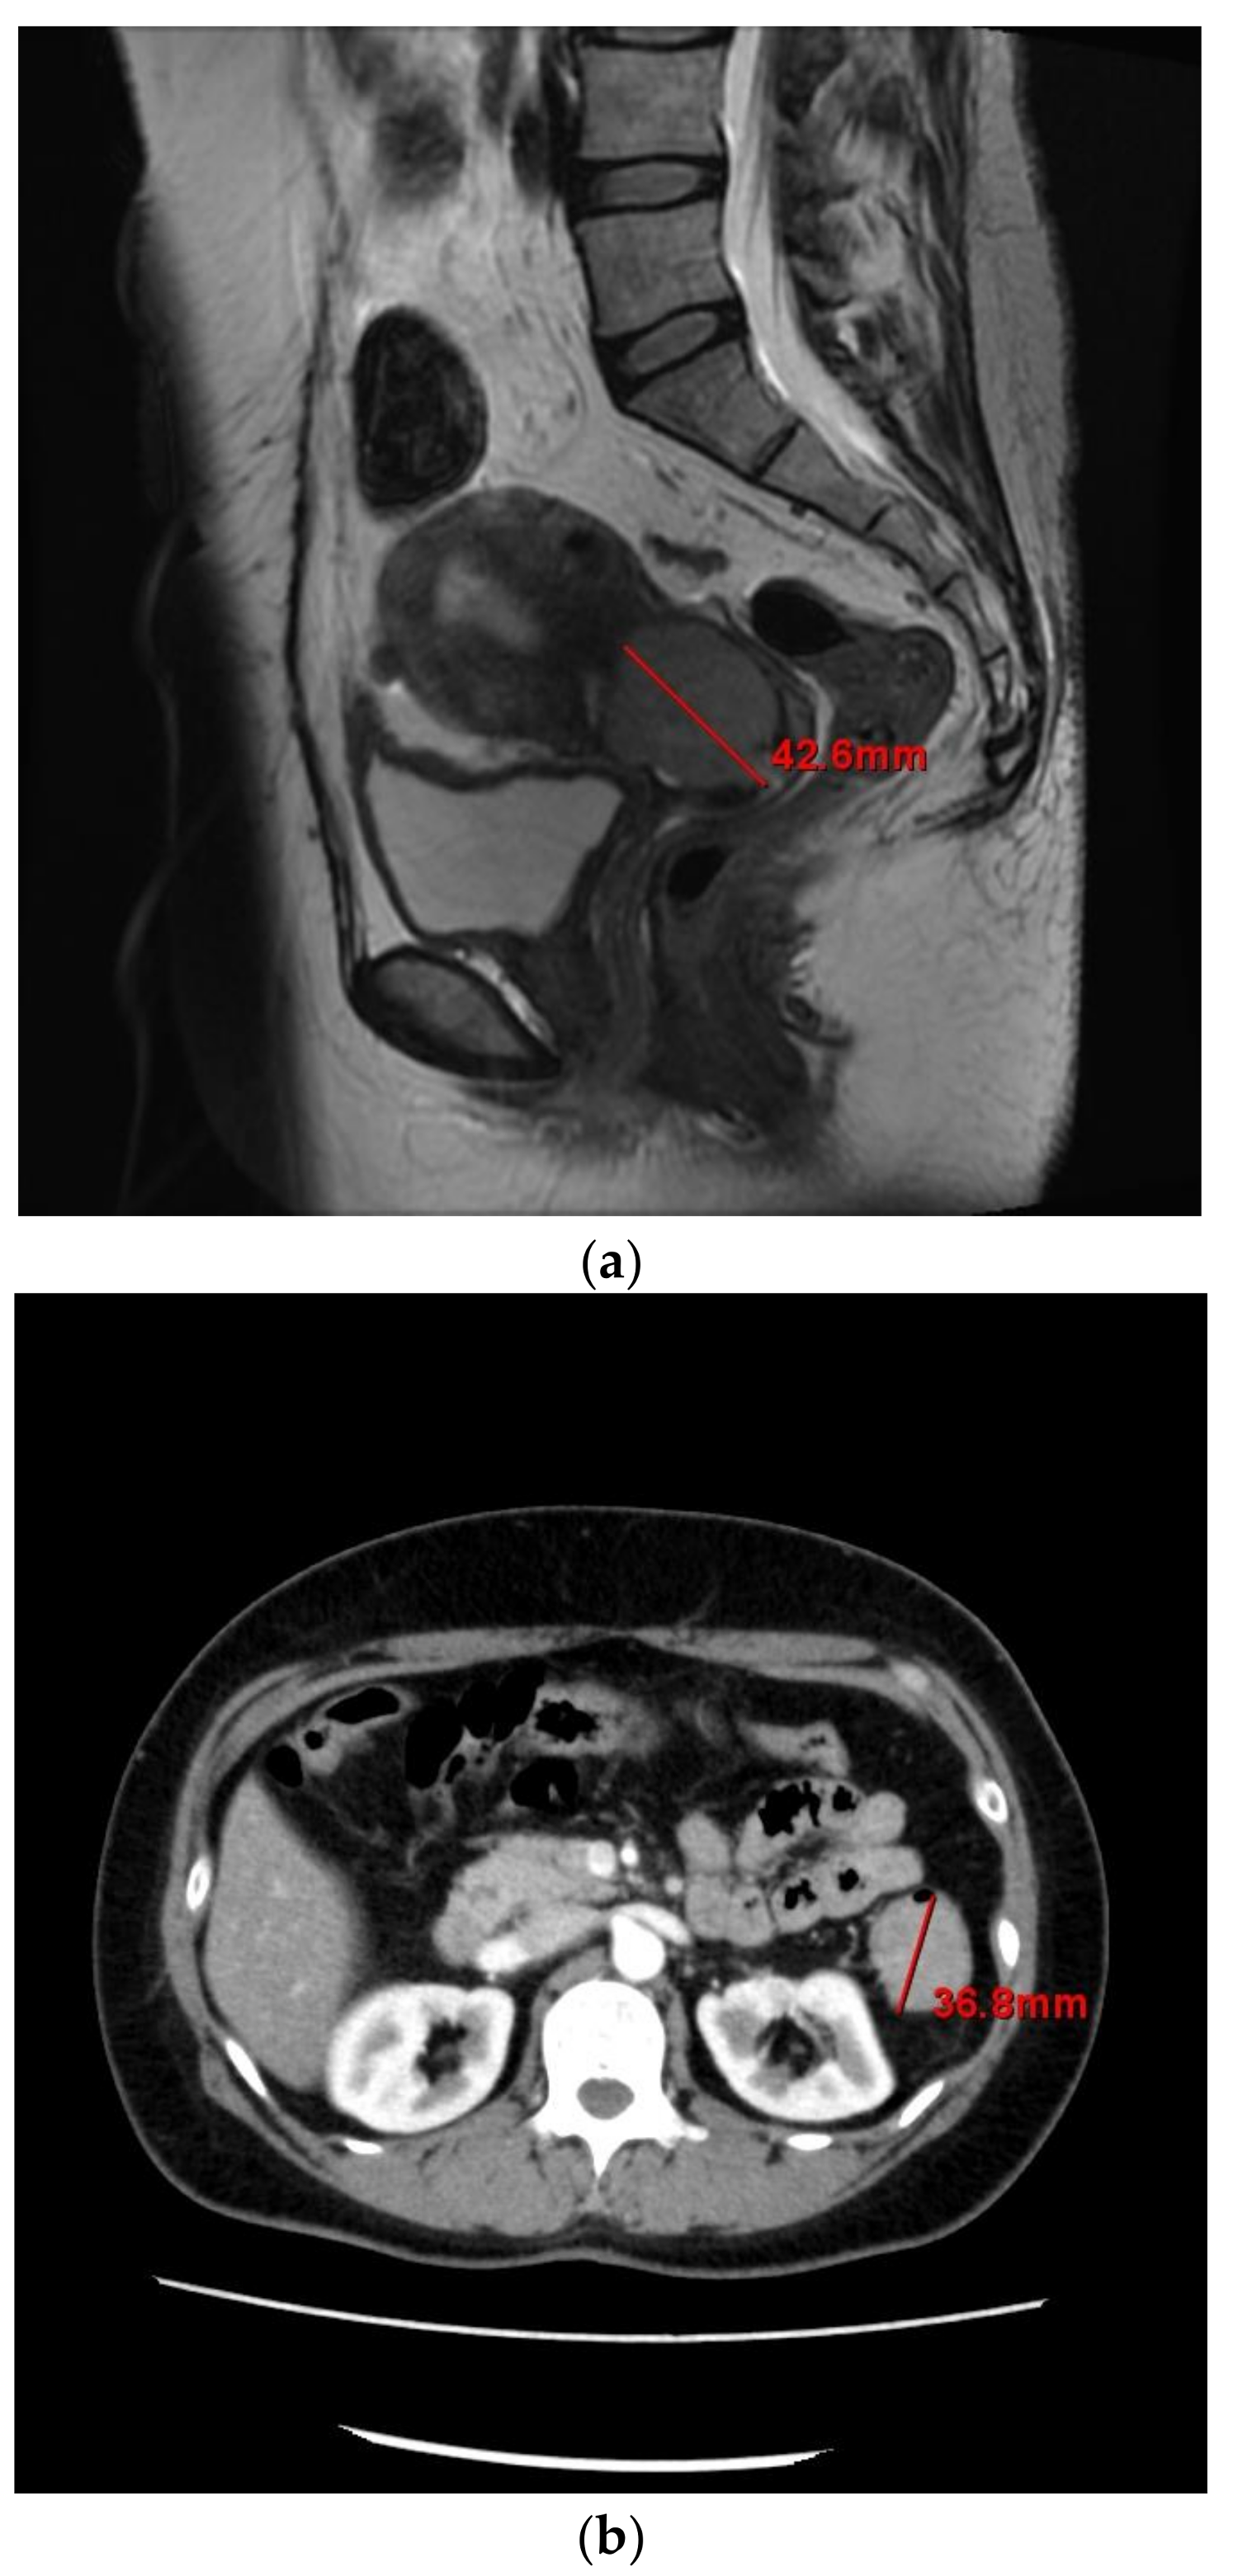

Pelvic magnetic resonance imaging indicated a tumor in the endocervix measuring 42 × 32 × 38 mm (Figure 1a), and a tumor in the transverse colon measuring 36 mm in the largest diameter (Figure 1b). It did not show peritonitis carcinomatosa, ascites, dissemination nodules, or metastasis to other organs. Contrast-enhanced computed tomography (CT) showed no lymphadenopathy. These findings suggested colorectal metastasis from cervical cancer or double cancer (cervical and colorectal cancer). Positron emission tomography-CT showed abnormal 18F-fluorodeoxyglucose uptake in the cervix and colorectum.

Figure 1.

(a) Pelvic magnetic resonance imaging of the tumor in the endocervix; (b) Contrast-enhanced computed tomography of the abdomen showing the transverse colon tumor.